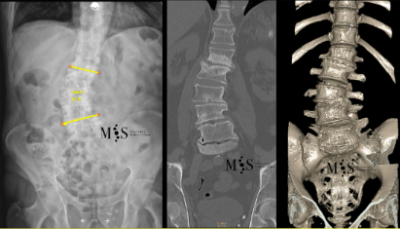

Scoliosis is a deformity/curving of the spine in the frontal plane. It can be congenital (present since birth) or degenerative (developed during the aging process). Progressive degeneration of the intervertebral disks (because of age, weight, activity, etc.) can lead to the spine to deform and curve in, ending up as a degenerative scoliosis, also called "de novo" because it is of "new" appearance in comparison to congenital scoliosis which has been present since birth.

Scoliosis lead to a curved back with the patient having problems walking with a straight back, and it can lead to an intense back pain. The spinal deformity and curving can lead to an impingement of the nerve roots which can cause radiating leg pain.

In these painful cases, surgery is indicated to (partially) correct the deformity and mainly to reduce/eliminate the pain generated by the scoliosis. In the most severe scoliosis cases an osteotomy (chiseling of a vertebral bone) may be required to straighten up the spine and reduce its deformity.

At the Morgenstern Institute of Spine we use the most advanced surgical endoscopic and percutaneous techniques to correct the degenerative scoliosis and speed up the patient’s recovery time. Hospital discharge is usually just a few days after surgery.